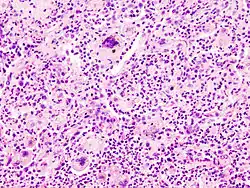

Una célula gigante contra cuerpo extraño es una colección de macrófagos fusionados (célula gigante) los cuáles se generan en respuesta a la presencia de un cuerpo extraño grande.[1] Esto es particularmente evidente con implantes que causan inflamación crónica y respuesta contra cuerpo extraño.[2] Esta reacción contra el implante causa daños a la zona infectada, dejando la superficie exterior con cicatrices.[3]

Los núcleos se encuentran desorganizados.[4] Estos se localizan en el centro celular y se superponen unos con otros.[5] Esto contrasta con la célula gigante de Langhans, donde los núcleos están organizados en el borde de esta.

Micrografía donde se aprecia un cuerpo extraño envuelta por una célula gigante. Tinción hematoxilina-eosina. -